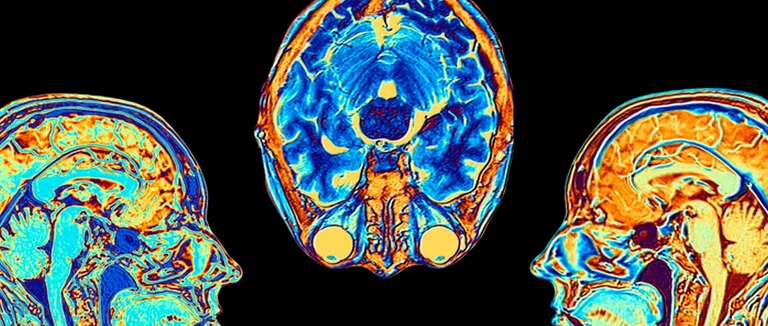

Tests d'imagerie (CT, MRI)

La tomodensitométrie (CT) et l'imagerie par résonance magnétique (MRI) sont cruciales. Elles permettent de voir les ventricules cérébraux et de détecter les problèmes. Ces tests confirment l'hydrocéphalie et évaluent sa sévérité.